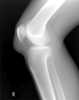

Adenosine deaminase deficiency with severe combined immunodeficiency and chondro-osseous dysplasia

Metaphyseal irregularity

Metaphyseal sclerosis